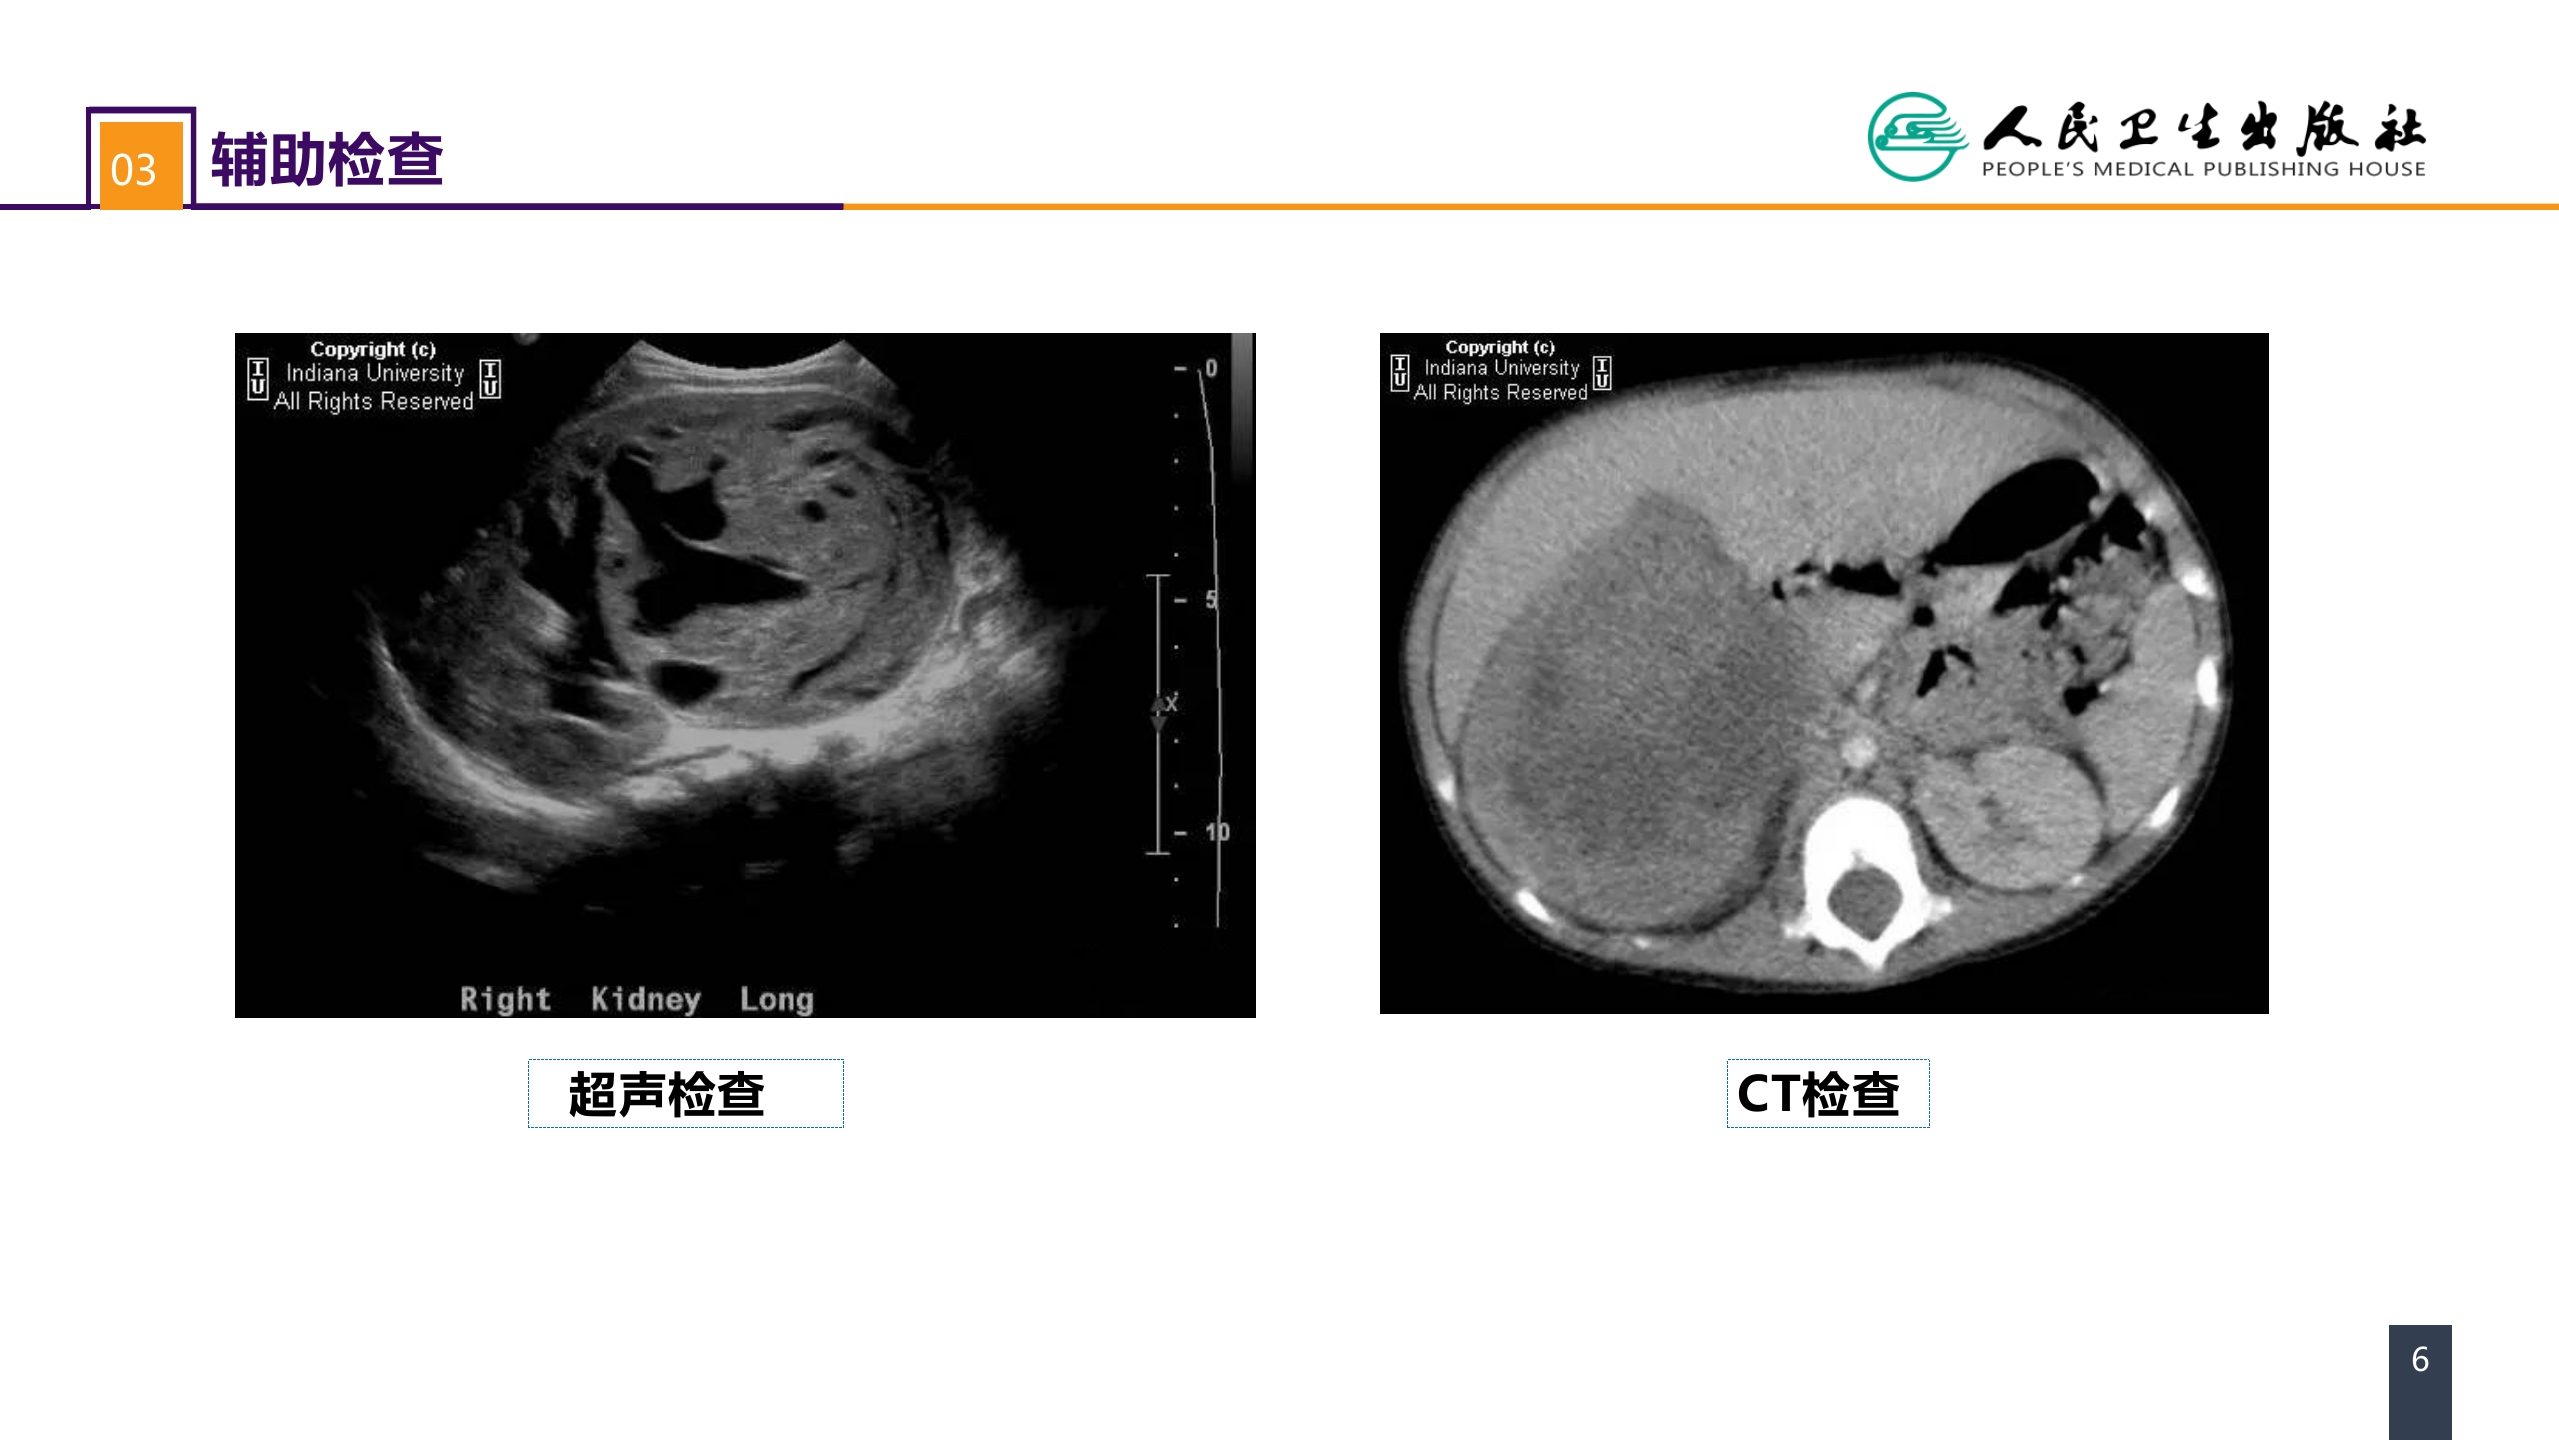

第五十三章 泌尿、男生殖系统肿瘤 案例分析-肾母细胞瘤